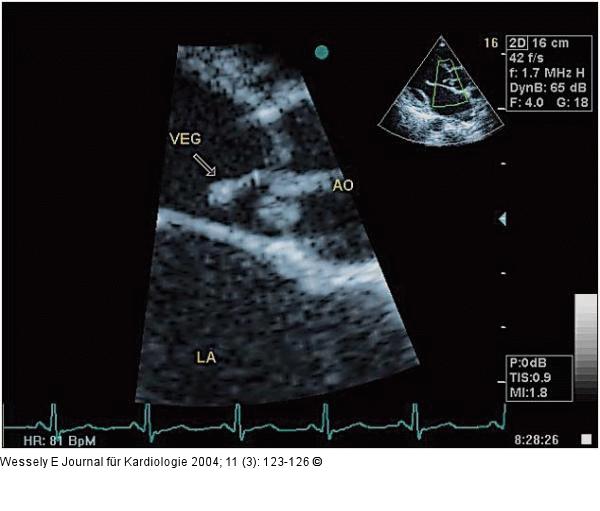

Abbildung 1: Aortenklappeninsuffizienz - Endokarditis Endokarditische Vegetation (Veg) an der akoronaren Taschenklappe (Ao = Aorta ascendens; LA = linker Vorhof) |

Endokarditische Vegetation (Veg) an der akoronaren Taschenklappe (Ao = Aorta ascendens; LA = linker Vorhof) |